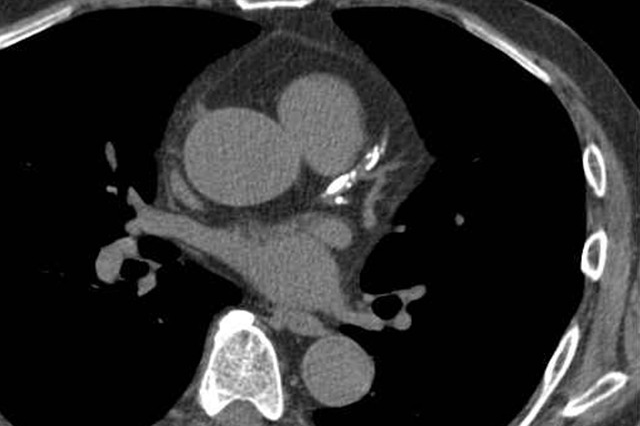

3. 혈관성 질환

혈관 질환은 응급 상황으로 이어질 수 있기 때문에 신속한 CT 진단이 필수적입니다.

- 폐색전증: 폐동맥에 혈전이 막히는 질환으로, 조기에 진단하지 못하면 생명을 위협할 수 있습니다. CT 폐혈관조영술은 폐색전증을 확인하는 가장 정확한 검사법입니다.

- 대동맥류·대동맥 박리: 흉부 대동맥이 늘어나거나 찢어지는 응급질환입니다. CT는 파열 여부, 박리된 층의 위치와 범위를 실시간으로 확인할 수 있습니다.

4. 심장 및 흉부 구조 이상

흉부 CT는 심장 자체보다는 주로 심막, 혈관, 구조적 이상을 평가하는 데 사용됩니다.

- 심막 질환: 심막삼출, 심막염 등 확인 가능

- 심장 비대: 심장 크기와 구조적 이상 파악

- 선천성 심장 기형: 대혈관 위치 이상, 폐정맥 기형 등 발견